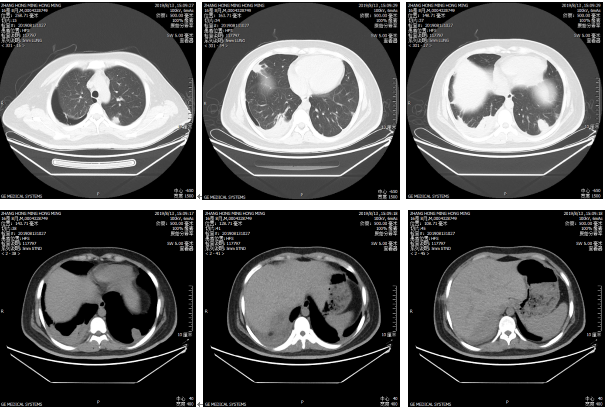

现病史:患者女性,41 岁,个体,河北省保定市人,主因间断发热、头痛 20 天,咳嗽、咳痰 2 周于 2019-7-25 入院。患者 20 天前「中暑」后出现发热,体温最高 39℃,畏寒、寒战,头痛,无呕吐,无咳嗽、咳痰、腹痛、腹泻等不适,自服「退热药」(具体不详)3 天,热退后体温复升。于当地诊所输液治疗(具体不详)3 天,头痛加重,恶心、非喷射性呕吐,呕吐物为胃内容物,无烧心、反酸,无咳嗽、腹泻。2 周前于当地医院查血常规:WBC 22.9×109/L、NE 91.1%;尿常规:白细胞 2+、蛋白+、酮体 3+、尿糖 4+;肝功能:ALT 57U/L、AST 28U/L、ALP 201U/L、GGT 102U/L;GLU 16.29 mmol/L。抗感染治疗(具体不详)3 天无效,仍发热,咳嗽、咳白粘痰,症状逐渐加重,出现前胸痛,波及双肩,未放射至后背、左臂、左手指,偶有呼吸困难。左眼视力模糊,无疼痛,右眼无异常。10 天前于本院急诊科查血常规示 WBC、NE 升高;CRP 191 mg/L、ESR 96 mm/h;NT-proBNP 792pg/ml;胸腹盆 CT 平扫:1. 双肺内见多发大小不等结节灶,转移瘤不除外 2. 心包少量积液,双侧少量胸腔积液 3. 肝右叶混杂低密度影(图 1);头颅 MRI 平扫:提示急性及亚急性多发腔隙性脑梗塞。考虑「肺部感染、急性脑血管病、肺多发结节」,给予「长春西丁、奥拉西坦、依达拉奉、对乙酰氨基酚、布洛芬」等对症治疗,最高体温降至 38.3℃ 左右,但咳嗽、呼吸困难加重,氧合指数 291。肝组织活检提示微脓肿形成,血培养回报肺炎克雷伯杆菌(药敏试验显示二三代头孢菌素敏感,哌拉西林敏感,亚胺培南敏感)。进一步行脑脊液常规及生化检查无明显异常;PCT 2.58ng/ml;血 GM 试验阴性;痰抗酸染色阴性。急诊及外科重症医学科考虑「肺部感染」,给予「美罗培南+万古霉素+更昔洛韦」抗感染治疗,并化痰、提高免疫功能等治疗,患者氧合功能改善,体温降至正常,但仍咳嗽、咳白粘痰,头痛、左眼痛、肝区痛,转入呼吸普通病房继续治疗。

图 1 病例 1 胸腹部 CT 平扫(2019-7-15)